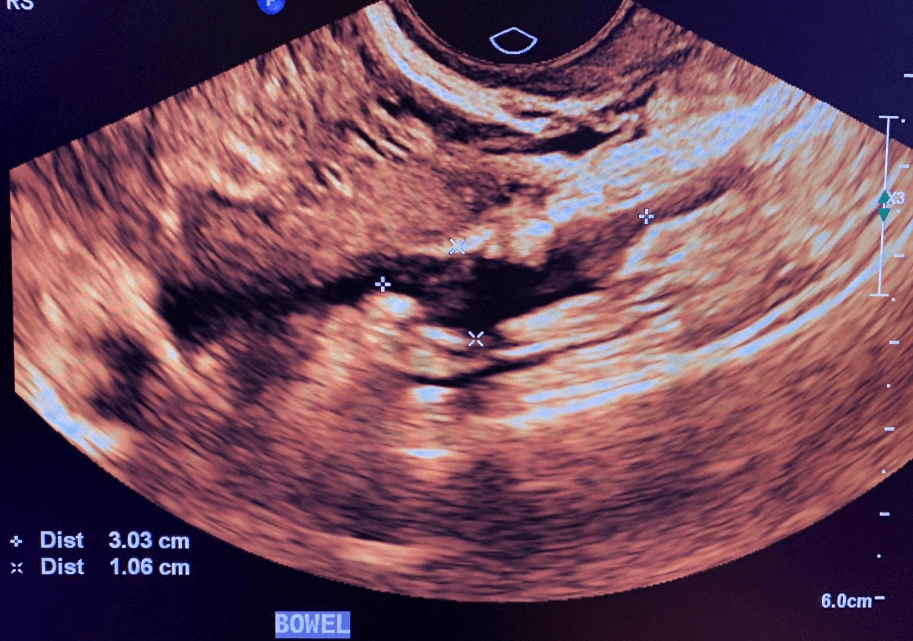

Rectosigmoid endometriotic nodule

- Rectosigmoid colon nodules